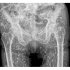

米フロリダ州の救急医がXに投稿…「最も異常なX線写真」が示す教訓

どうしてこんなことに?!(サム・ガリ医師のXから)